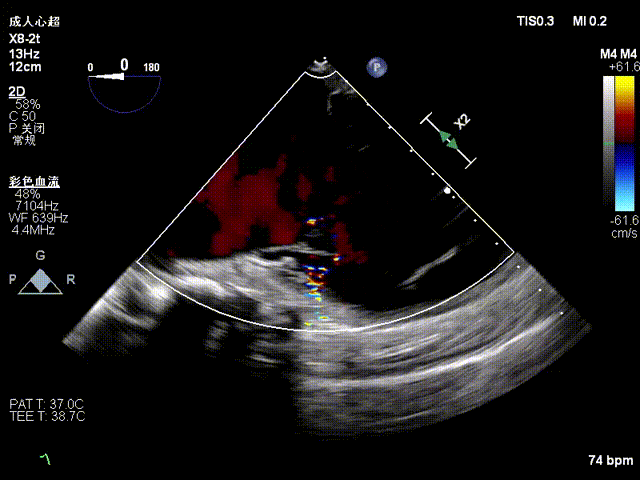

Echocardiographic findings indicated: Type IIIB quadrileaflet tricuspid malformation with extremely severe tricuspid regurgitation (5+, vena contracta: 16.1 mm on average). Regurgitant orifices were located at the anterior-septal, central, and posterior-septal regions, with a 11 mm central gap, leaflet tethering (tethering height: 10 mm), and tricuspid annular dilatation (mean annular diameter: 53 mm). The inferior vena cava diameter was approximately 25 mm, and RV FAC was 40%.

Baseline regurgitation after anesthesia